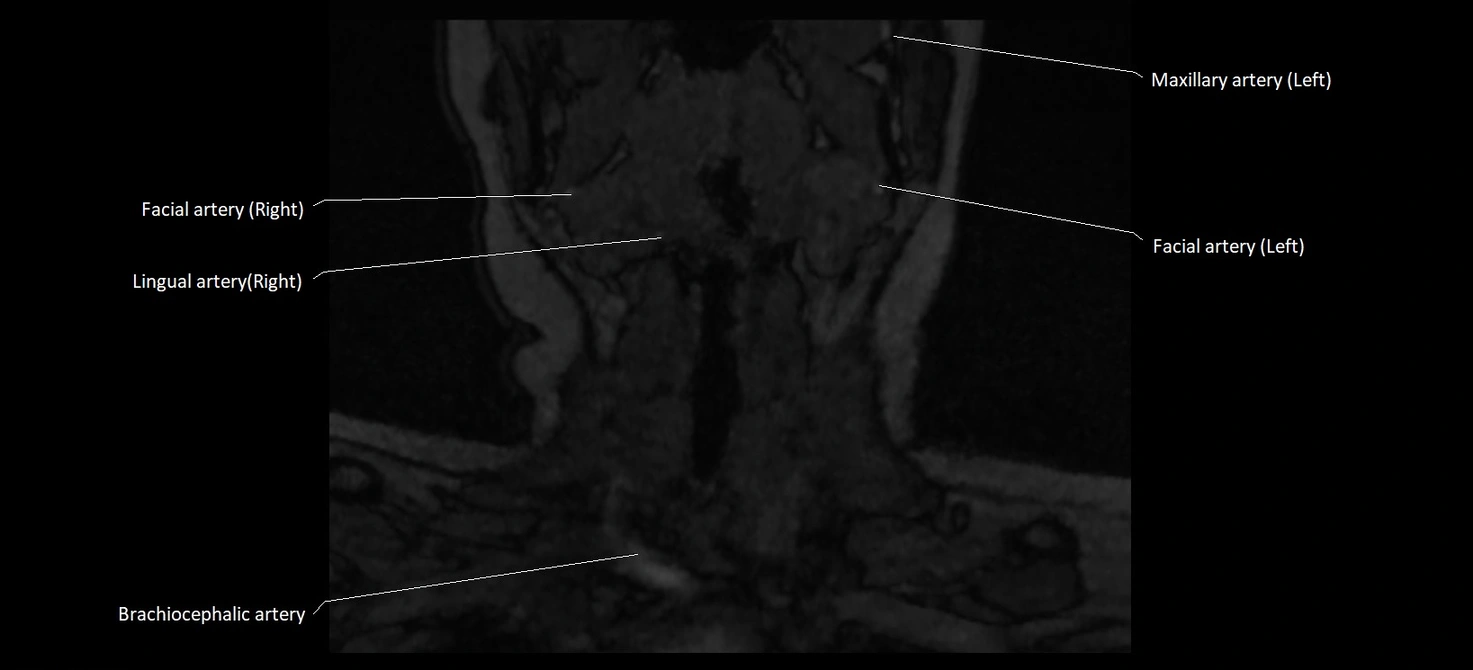

CT image

image